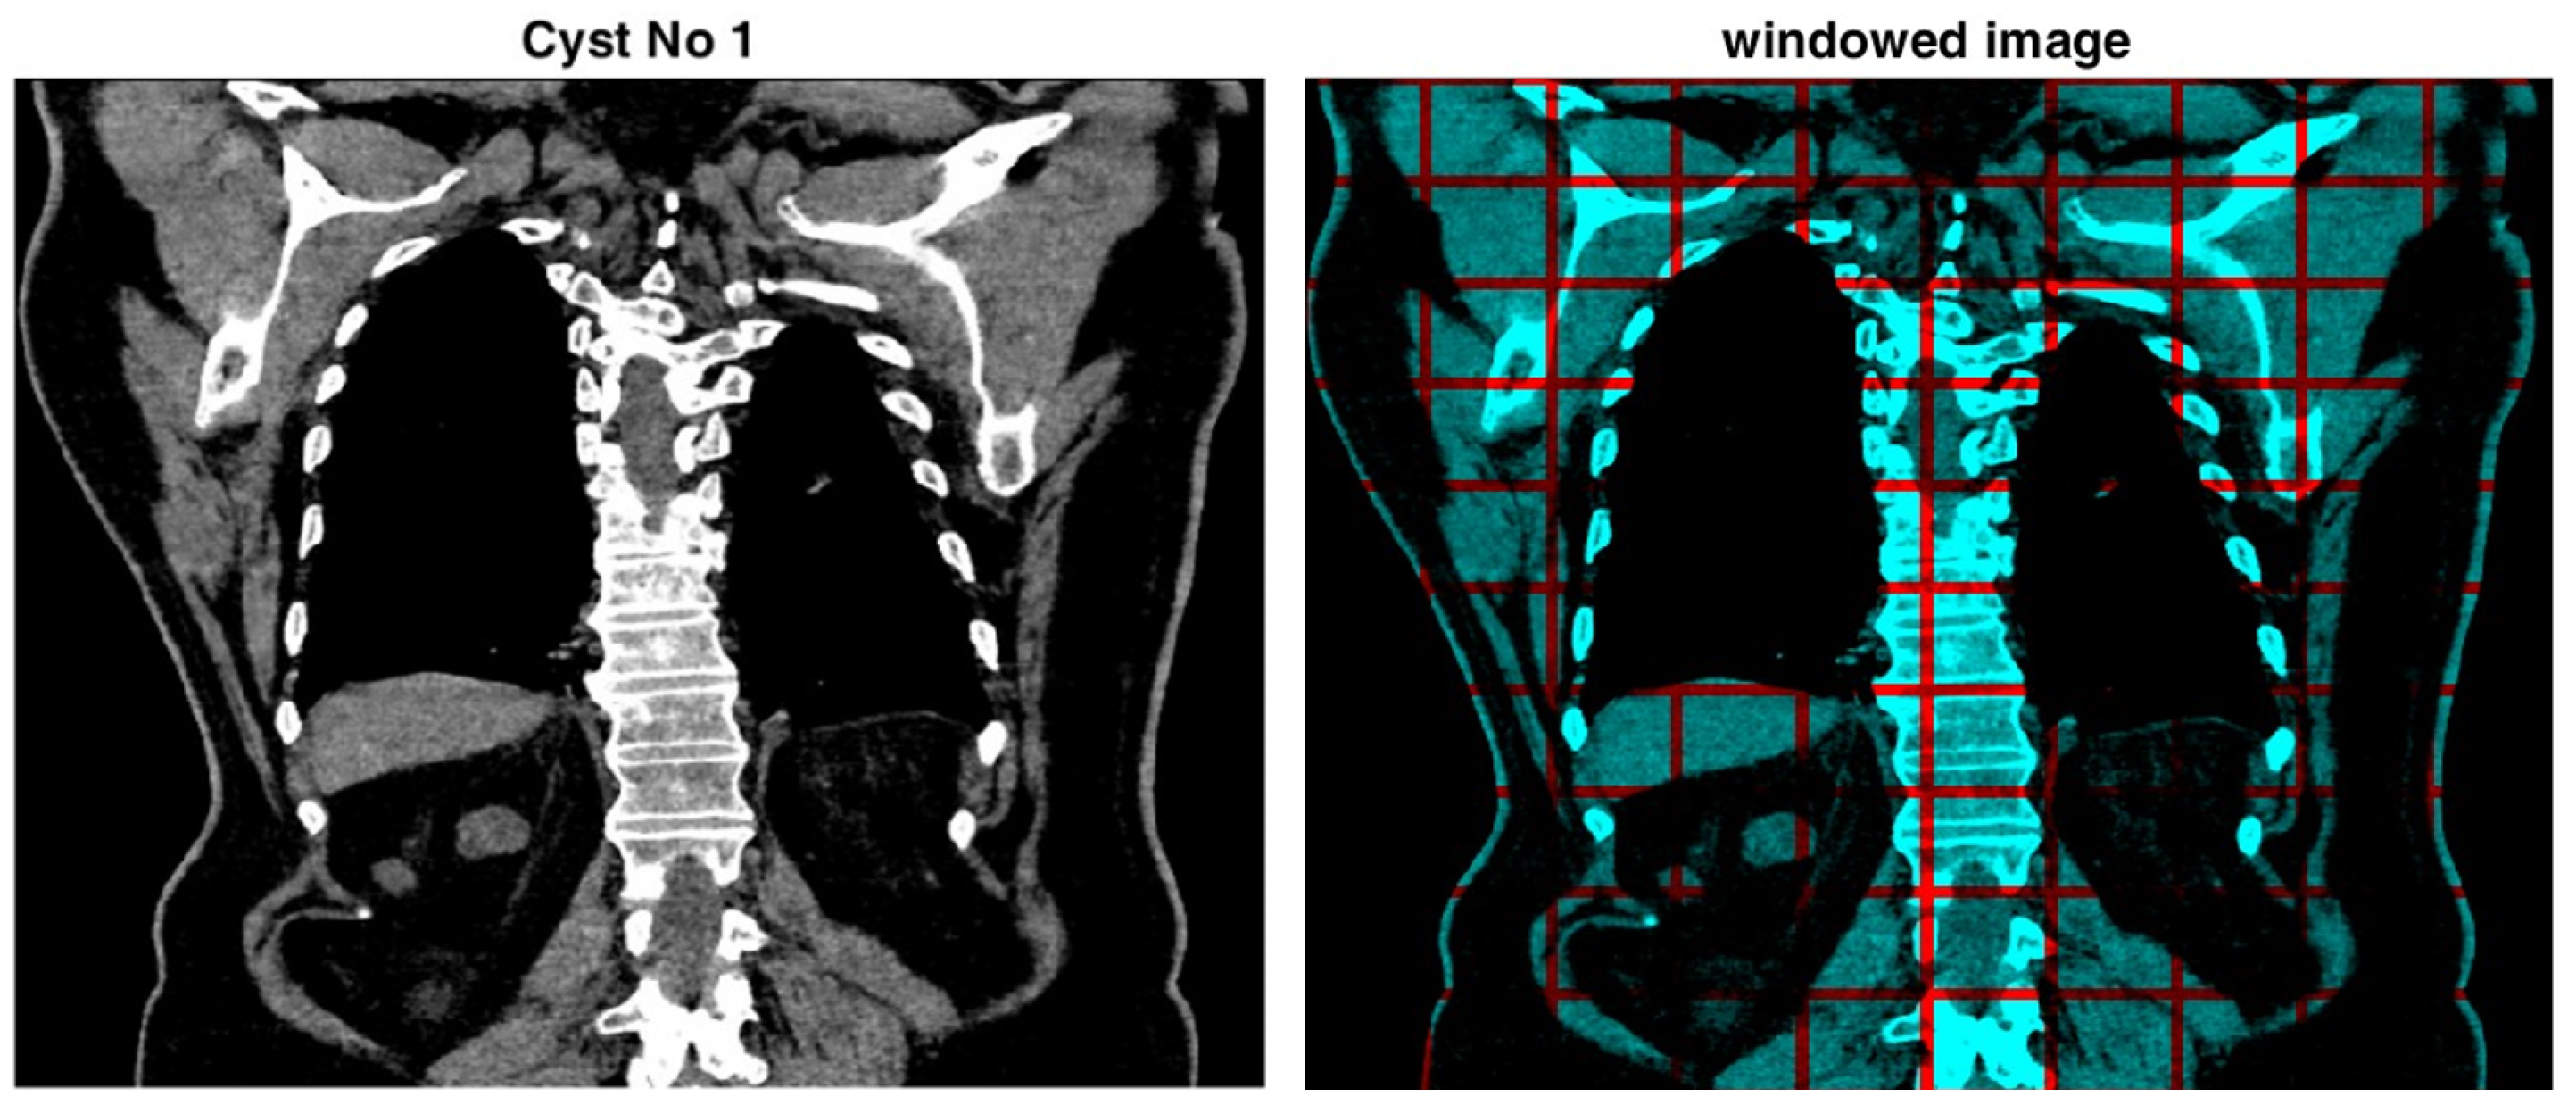

3.2. Local Histogram with Asymmetric Intervals